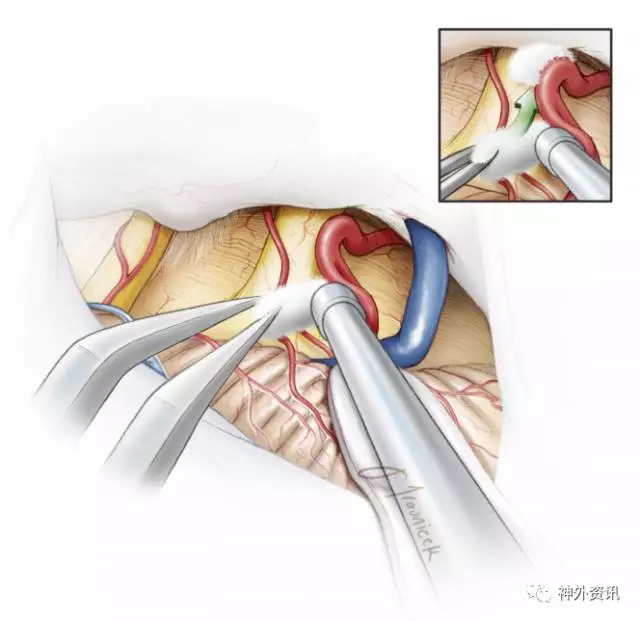

图7. 在岩-幕交界处下部往内下方向牵引小脑。

剪一小片手套(剪成略大于脑棉)作为橡胶垫片,保护小脑半球免受脑棉摩擦所致的潜在的损伤。笔者会将胶片平行且稍低于天幕与岩尖交界处(沟)并朝着岩骨方向下方放置。辨别这些标记以预防:1)小脑上桥静脉意外暴露(或由此产生的撕裂),2)将牵开器直接放到面听神经复合体的下方。

轻柔向内下方牵拉小脑半球,暴露岩上静脉。锐性打开静脉下方的蛛网膜,释放多余脑脊液。为了保护岩静脉及面听神经,应该使其上覆盖的蛛网膜保持完整。

用吸引器轻柔地动态牵拉,在岩上静脉下方往外侧牵拉小脑半球,使静脉略有张力。这种方式足以提供所需的操作空间,极少需要牺牲岩上静脉。灵活使用吸引器有利于选择性暴露必要的手术空间,取得三叉神经REZ区合适的操作角度。避免了使用脑组织牵开器以及岩上静脉的牺牲。

图8. 小心切开蛛网膜和正确地辨别神经很关键。注意保留脑干周围的血管。分离深部的蛛网膜应谨慎,首先用球头剥离子分离缠绕的血管(上图)。三叉神经比面听神经复合体位置更深、更靠近内侧。面听神经复合体位置则相对表浅,斜向下或向上走行,不要误认为是三叉神经(下图)。

图9. 细致地锐性分离蛛网膜,暴露三叉神经REZ区。